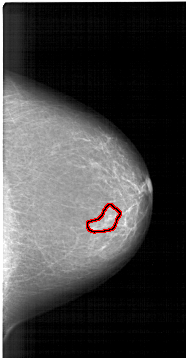

A_1422_1.RIGHT_MLO

FILE: A_1422_1.RIGHT_MLO.OVERLAY

TOTAL_ABNORMALITIES 1

ABNORMALITY 1

LESION_TYPE MASS SHAPE IRREGULAR MARGINS ILL_DEFINED

ASSESSMENT 4

SUBTLETY 1

PATHOLOGY BENIGN

TOTAL_OUTLINES 1

BOUNDARY